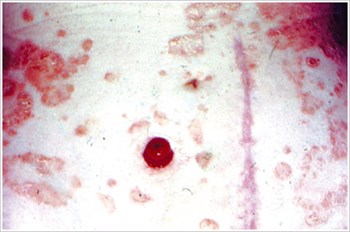

Pyoderma Gangrenosum

Popis/příčiny:

Zánětlivé kožní onemocnění, které se často vyskytuje u pacientů se zánětlivým onemocněním střev (IBD), jako je Crohnova choroba nebo ulcerózní kolitida.

Symptomy:

- Nepravidelně tvarované, červené, bolestivé, infikované vředy, s červenými až fialovými svinutými okraji; se objevují na nohou, hýždích, obličeji a peristomální oblasti.